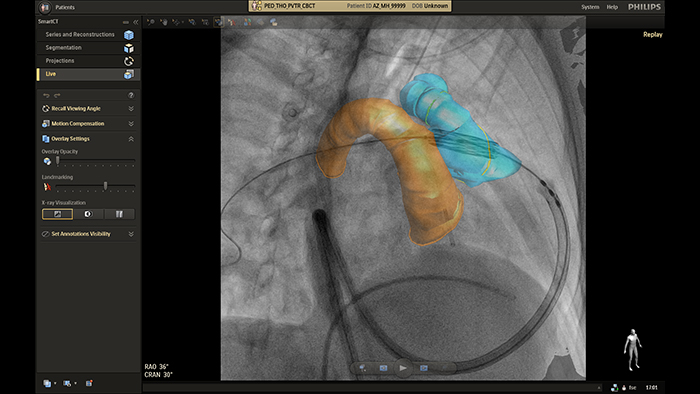

Descubra o SmartCT, o próximo passo para simplificar e avançar a imagem 3D na sala para doenças cardíacas congénitas

O software de aplicação clínica de terapia guiada por imagens SmartCT da Philips permite que qualquer utilizador clínico realize imagens 3D, independentemente do seu nível de experiência com imagens 3D*. Através do ecrã tátil na mesa, pode aceder a protocolos de aquisição 3D personalizados clinicamente e a ferramentas avançadas de visualização e medição que descrevem o tipo e a extensão da doença com grande detalhe. * O nível de especialização do utilizador necessário é descrito nas Instruções de utilização como o Perfil do operador previsto.

Orientação em tempo real do SmartCT